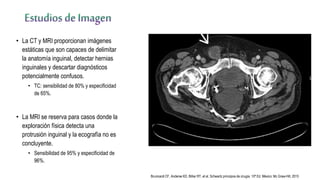

• La CT y MRI proporcionan imágenes

estáticas que son capaces de delimitar

la anatomía inguinal, detectar hernias

inguinales y descartar diagnósticos

potencialmente confusos.

• TC: sensibilidad de 80% y especificidad

de 65%.

• La MRI se reserva para casos donde la

exploración física detecta una

protrusión inguinal y la ecografía no es

concluyente.

• Sensibilidad de 95% y especificidad de

96%.